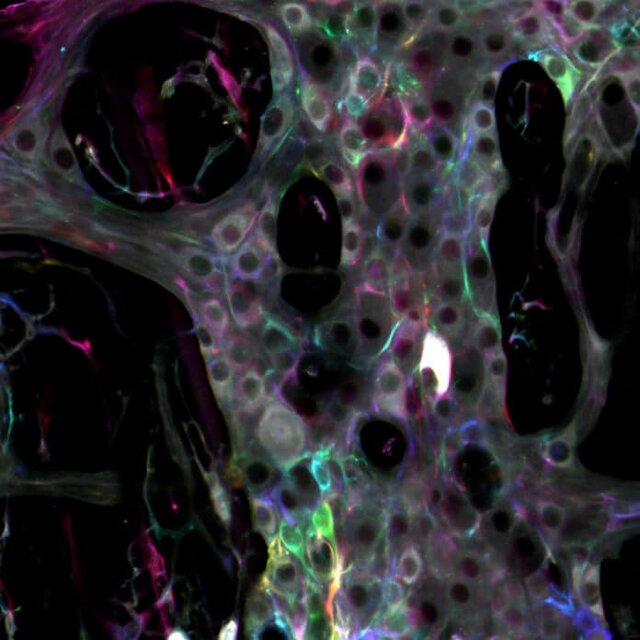

به گزارش از تی ای، سیستم عصبی رودهای برای مثال مغز دوم روده، یک شبکه پیچیده متشکل از نورونها و گلیا است که رودههای ما را پوشانده است. حال دانشمندان آمریکایی در مطالعه اخیرشان نشان دادهاند که سلولهای گلیا نقش بسیار فعالتری در سیستم عصبی روده دارند.

نتایج مطالعه جدید محققان حاکی از آن است که گلیا دقیقا بر سیگنالهای منتقل شده توسط مدارهای عصبی تاثیر میگذارند.

استاد "برایان گالبرانسن"(Brian Gulbransen) از دانشکده فیزیولوژی دانشگاه ایالتی میشیگان در این باره گفت: اگر مغز دوم را به عنوان رایانه در نظر بگیریم، میتوانیم بگوییم گلیا تراشههایی هستند که عملکرد حاشیهای دارند و عضو فعال پیام رسانی در شبکهاند و کار آنها تعدیل سیگنالها است و مانند نورونها نیستند. علاوه بر این عملکرد، گلیا این موضوع را تایید میکند که همه چیز بدون مشکل در حال انجام است.